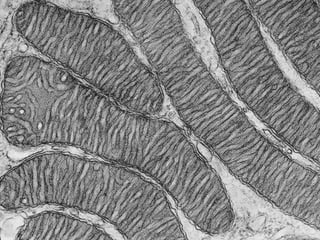

Este documento presenta imágenes microscópicas de diferentes tipos de tejidos y estructuras celulares teñidas con varios métodos histológicos. Incluye fotografías que muestran fibras de colágeno, elásticas y reticulares en diversos órganos, así como membranas basales y células especializadas de órganos como riñones, glándulas mamarias y próstata. El propósito es demostrar la aplicación de técnicas histológicas para visualizar componentes celulares y tej